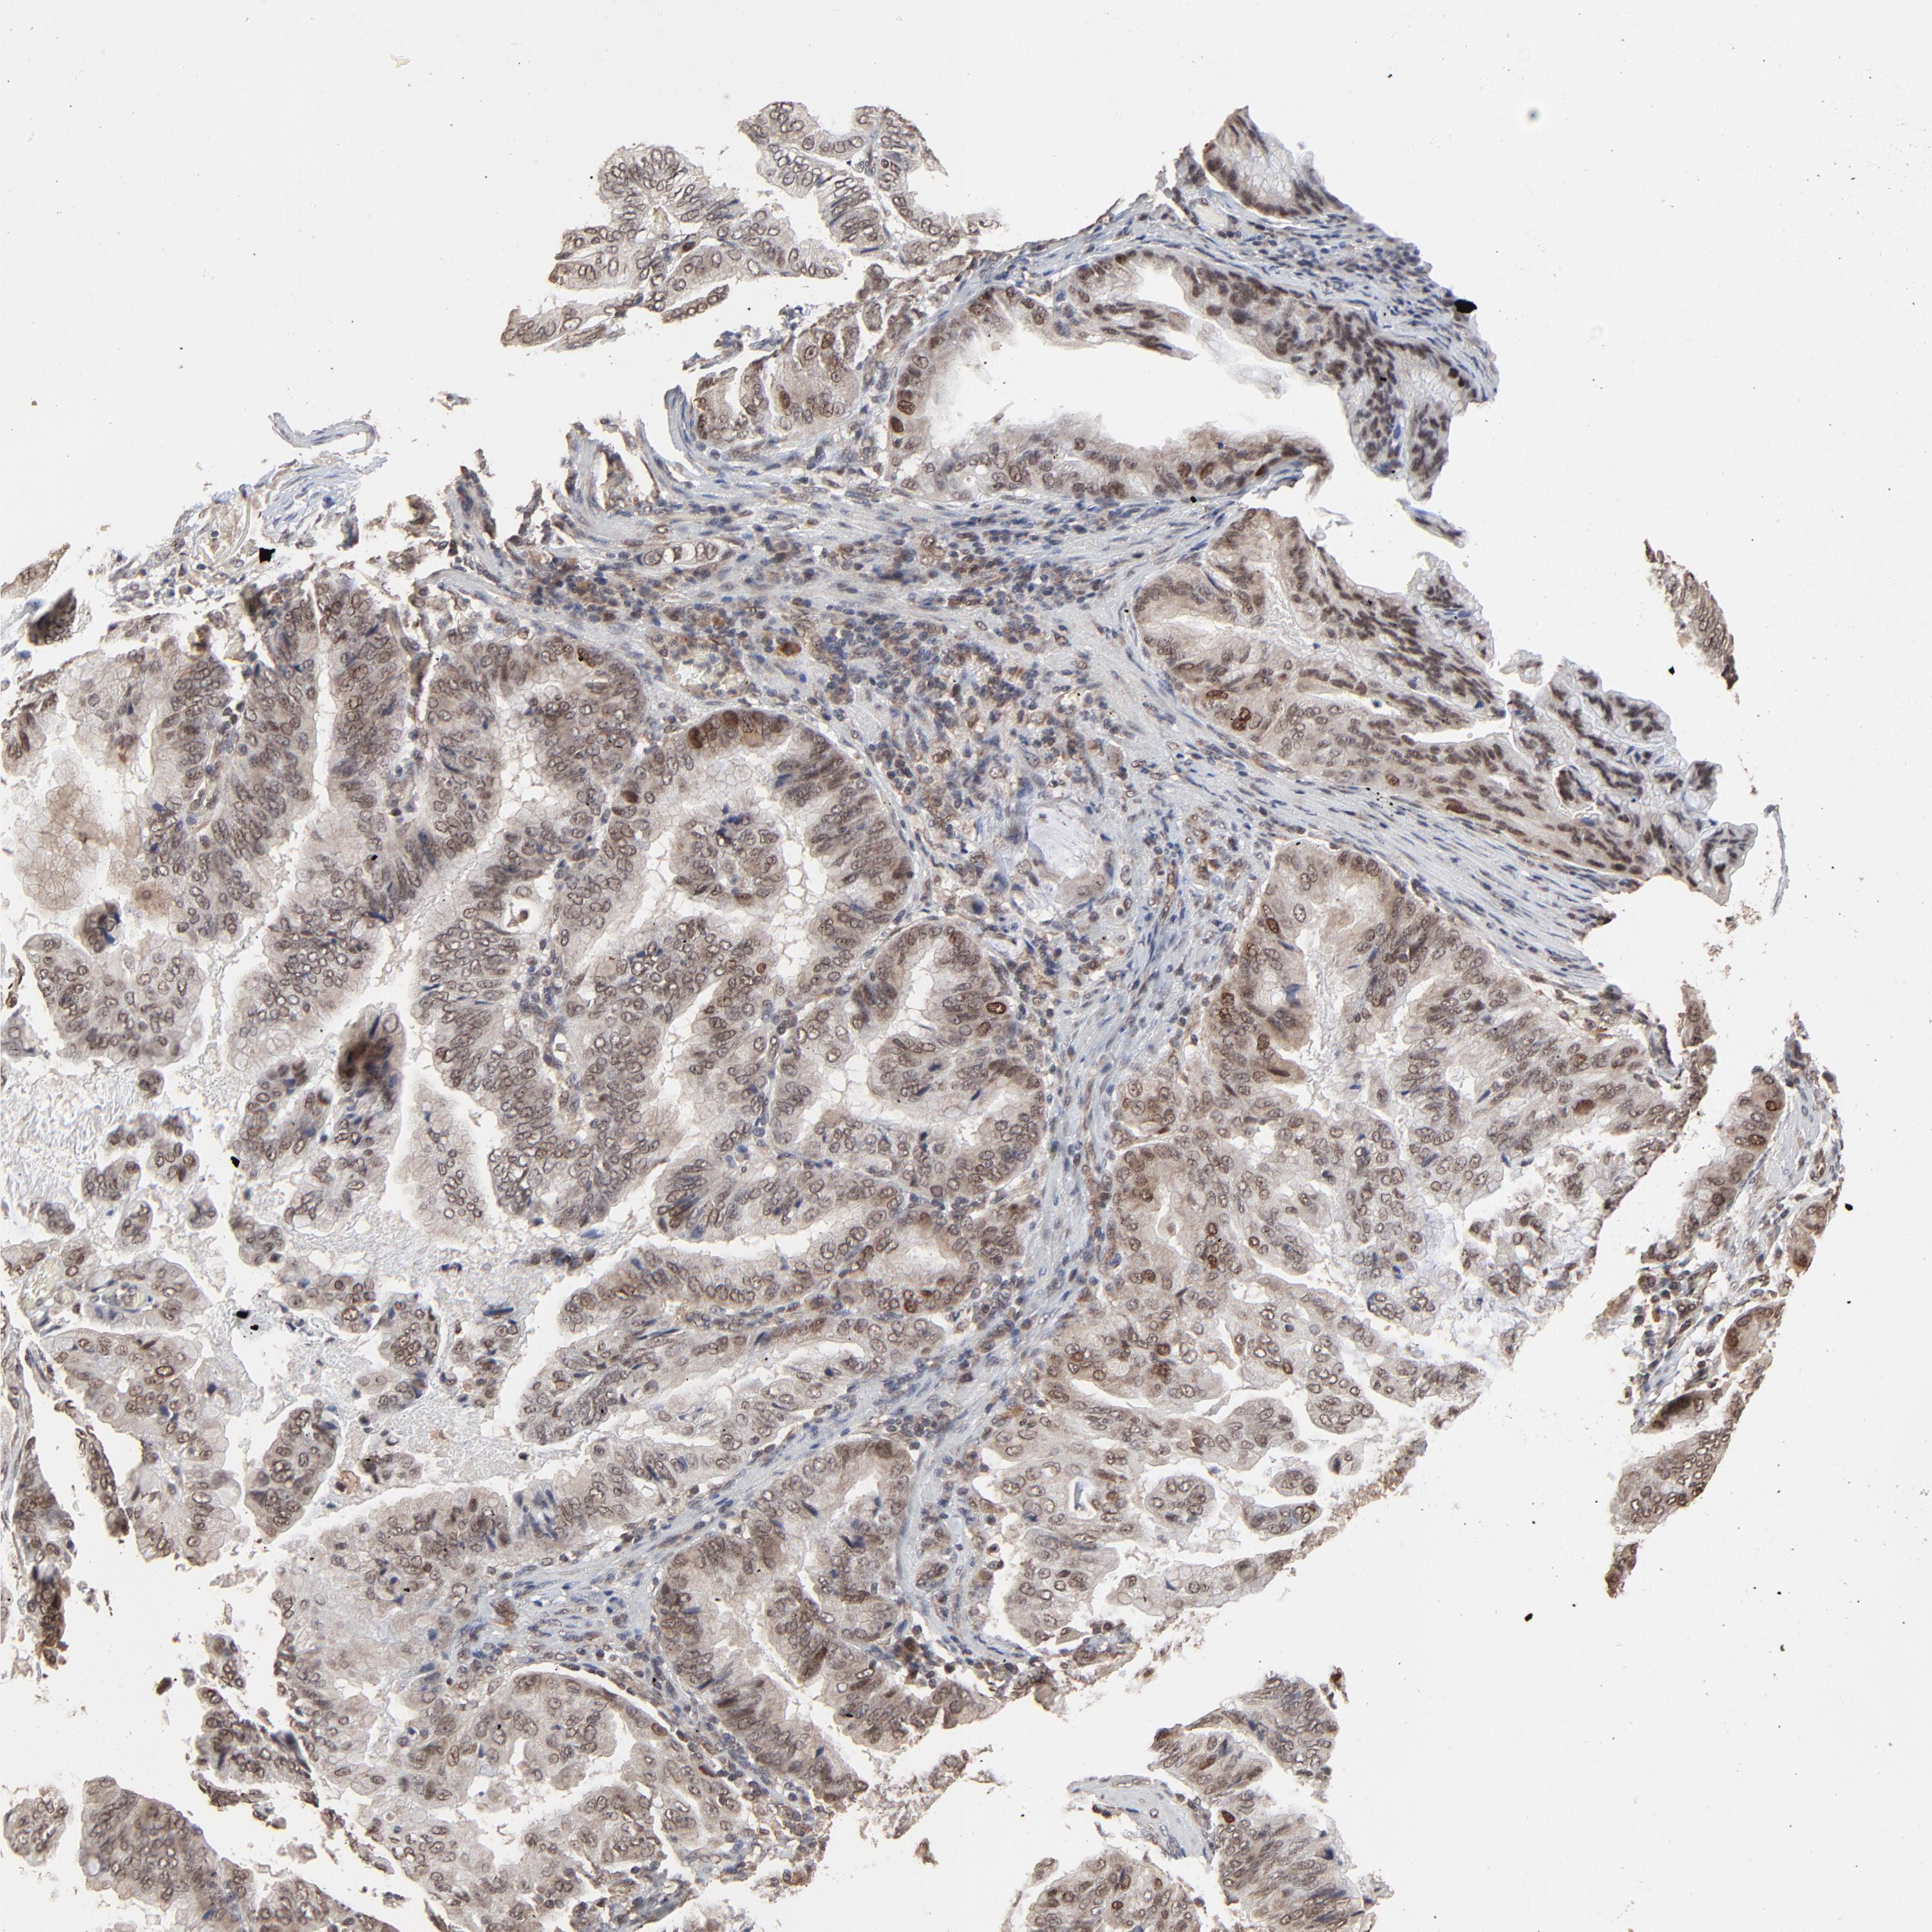

STOMACH CANCER - Protein expressioni

A mouse-over function shows sample information and annotation data. Click on an image to view it in a full screen mode. Samples can be filtered based on level of antibody staining by selecting one or several of the following categories: high, medium, low and not detected. The assay and annotation is described here.

Note that samples used for immunohistochemistry by the Human Protein Atlas do not correspond to samples in the TCGA dataset.

Antibody stainingi

Antibody staining in the annotated cell types in the current human tissue is reported as not detected, low, medium, or high, based on conventional immunohistochemistry profiling in selected tissues. This score is based on the combination of the staining intensity and fraction of stained cells.

Each image is clickable and will lead to virtual microscopy that enables deeper exploration of all samples and also displays staining intensity scores, fraction scores and subcellular localization as well as patient and tissue information for each sample.

Antibody HPA003077

Staining

High

Medium

Low

Not detected

Intensity

Strong

Moderate

Weak

Negative

Quantity

>75%

75%-25%

<25%

None

Location

Nuclear

Cytoplasmic/membranous

Cytoplasmic/membranous,nuclear

Adenocarcinoma, NOS